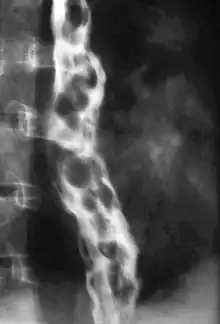

Esophageal varices are extremely dilated sub-mucosal veins in the lower third of the esophagus.[1] They are most often a consequence of portal hypertension,[2] commonly due to cirrhosis.[3] People with esophageal varices have a strong tendency to develop severe bleeding which left untreated can be fatal. Esophageal varices are typically diagnosed through an esophagogastroduodenoscopy.[4]

Dilated submucosal veins are the most prominent histologic feature of esophageal varices. The expansion of the submucosa leads to elevation of the mucosa above the surrounding tissue, which is apparent during endoscopy and is a key diagnostic feature. Evidence of recent variceal hemorrhage includes necrosis and ulceration of the mucosa. Evidence of past variceal hemorrhage includes inflammation and venous thrombosis.